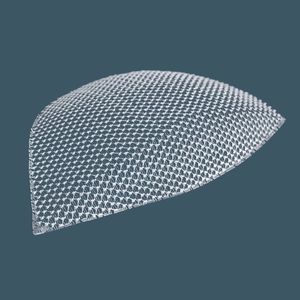

... 2P-UCMC ist eine transparente, leichte, ultradünne, nicht resorbierbare chirurgische Prothese aus Polypropylen, die aus einem monofilen makroporösen Netz und einer transparenten Folie besteht. Indikationen: Behandlung ...